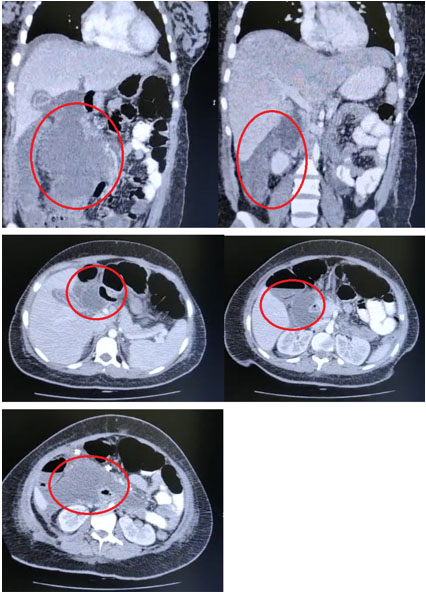

The patient continued to experience abdominal pain in the postoperative period. She presented with persistent tachycardia and a greenish-yellow fluid in the drainage, prompting an abdominal tomography on the second day after surgery (Figure 1), revealing free fluid and collections between the intestinal loops without hepatic lesions or other alterations. The surgeons decided to perform another laparotomy, revealing biliary peritonitis of the four quadrants without alterations in the gallbladder or bile duct. The intestine was intact; however, bile seemed to originate from the hepatic hilum with no apparent source. Subsequently, a subhepatic drainage was inserted, and the patient was transferred to a higher care hospital for further diagnostic workup.

Figure 1: Contrast computed tomography of the abdomen.

In abdominal computed tomography or ultrasound, indirect signs of a CBD perforation can be seen, such as a compressed gallbladder (empty gallbladder), perihepatic collections, or intra-abdominal free fluid. However, in most cases, there is no evidence of the exact perforation site. In some case series, the presurgical diagnosis was set up with magnetic resonance cholangiopancreatography or ERCP [11],[12]. Retrospectively, we found in our case the aforementioned tomographic signs. However, these signs are not specific for a CBD perforation, and due to the low incidence of spontaneous CBD perforations, the diagnosis was not made or even suspected in the presurgical setting.